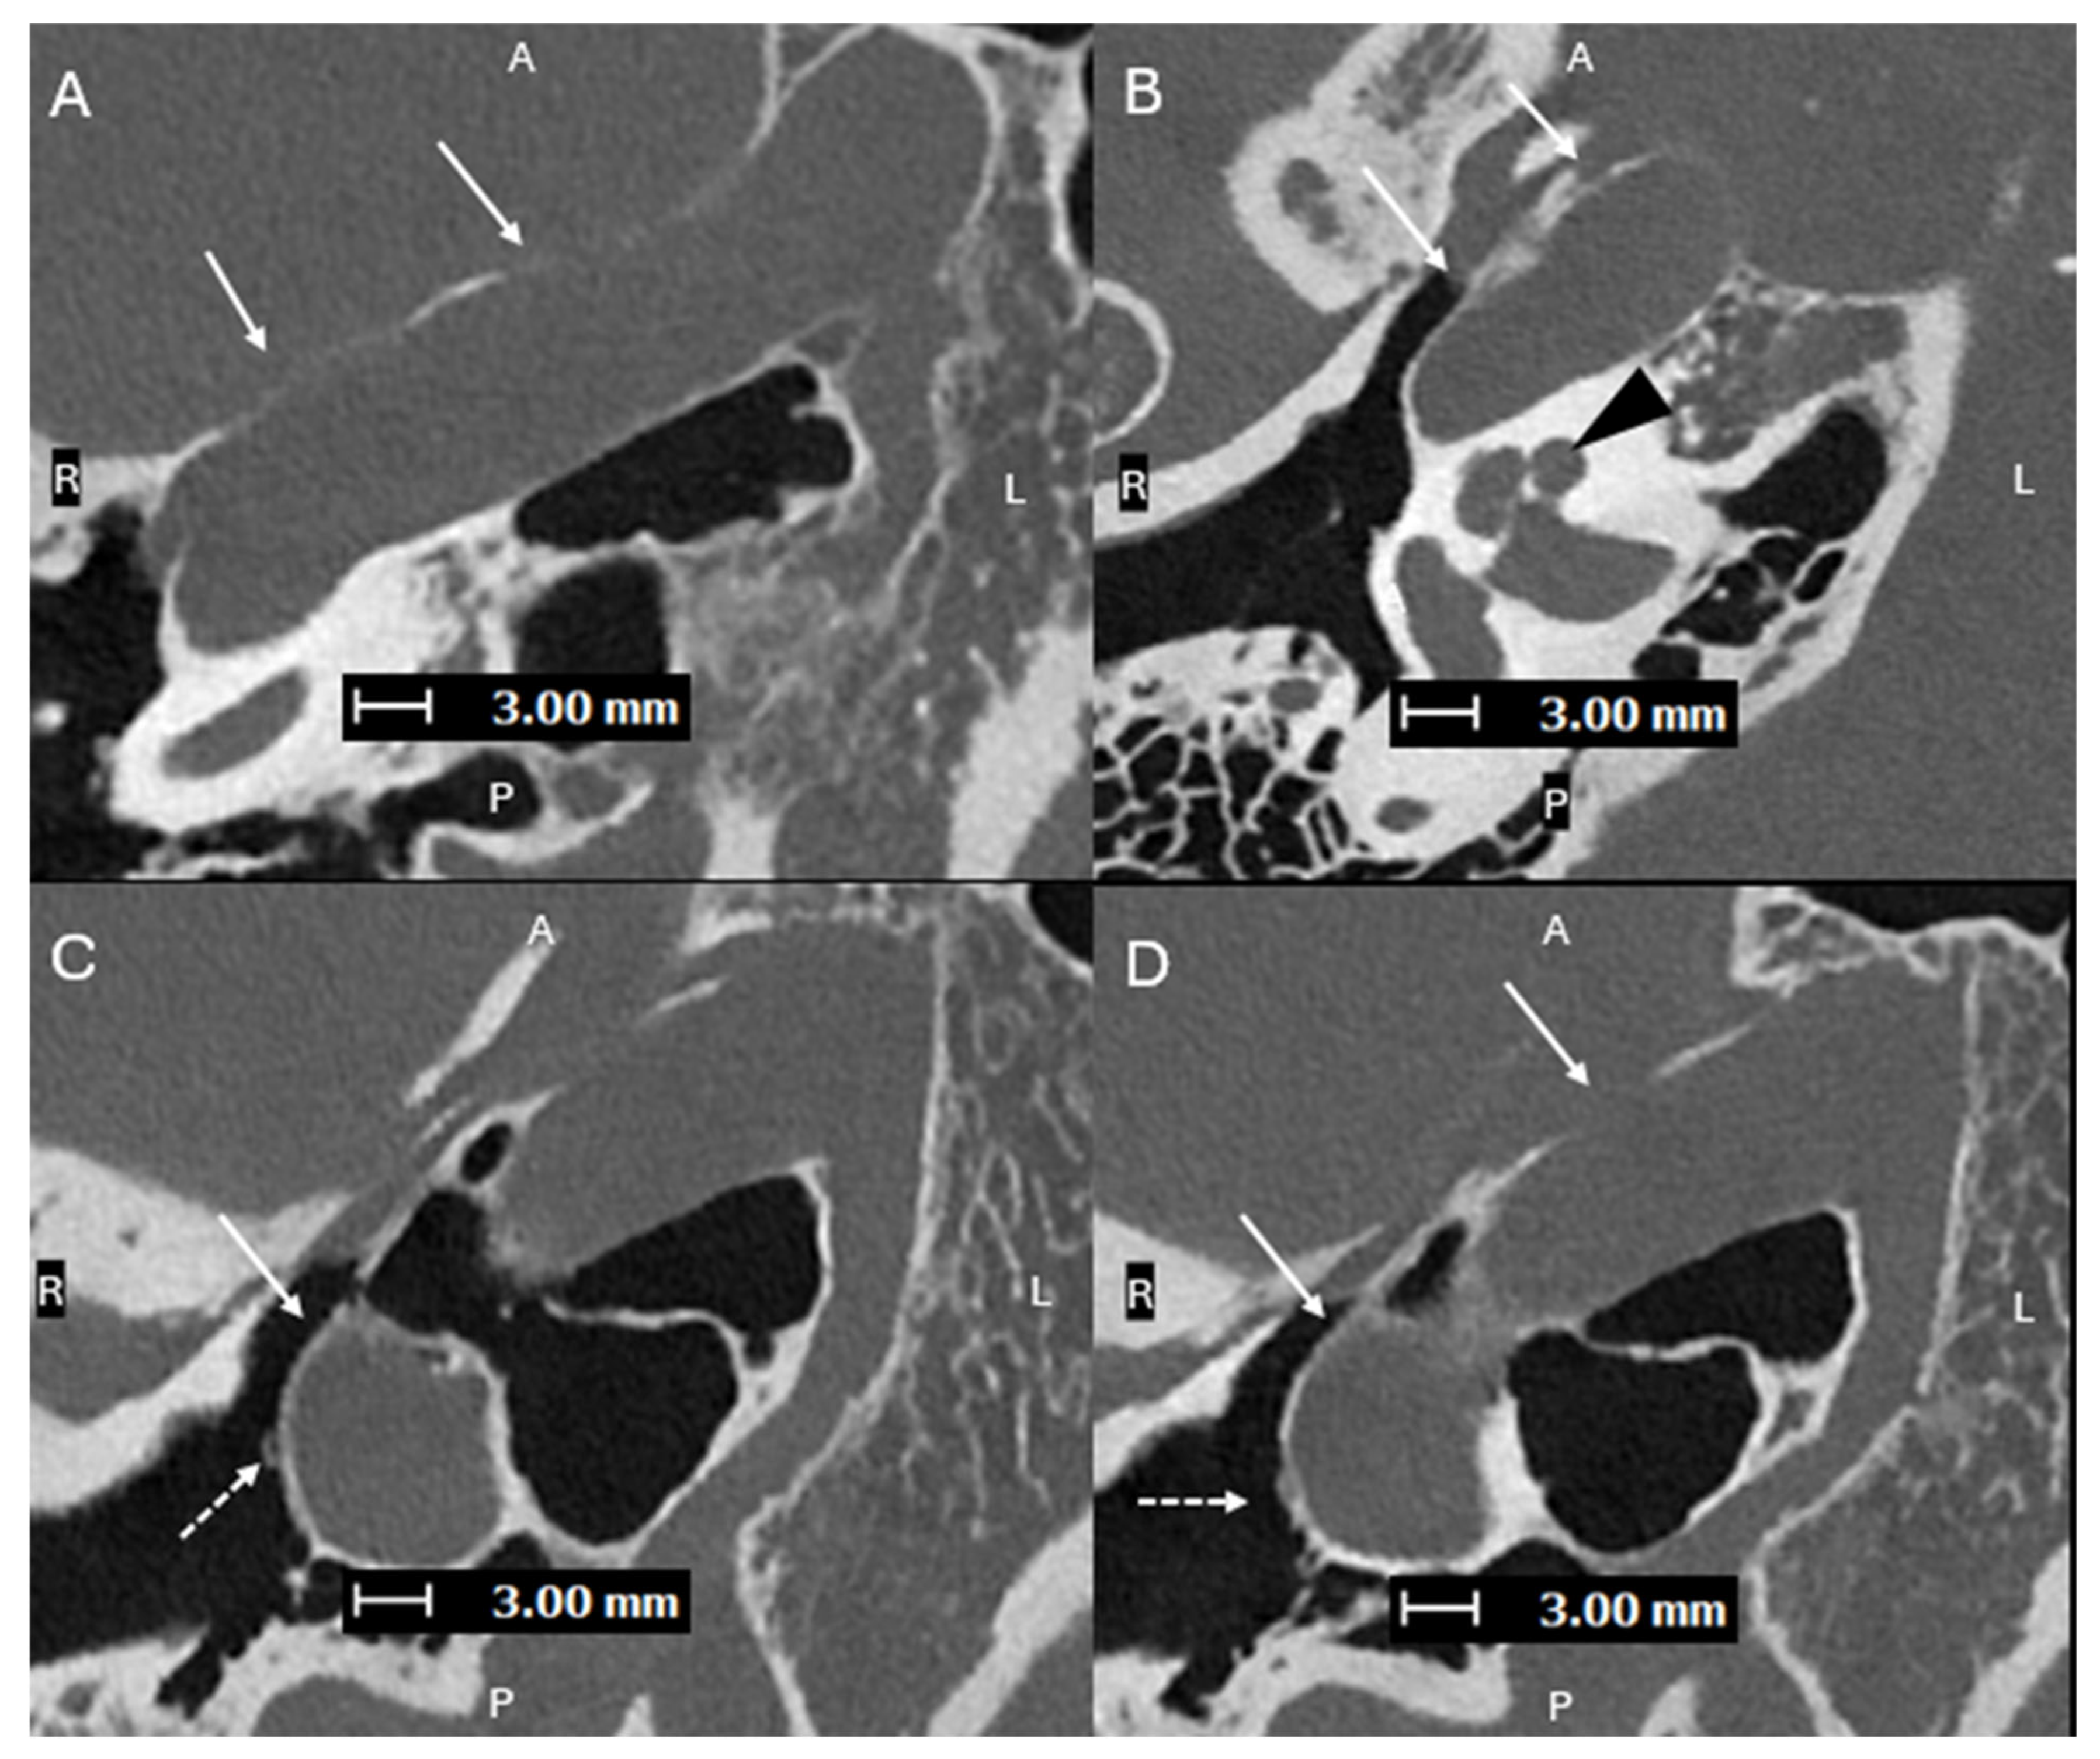

Figure 4. Axial oblique images (superior to inferior (AC), with A, P, L, R for orientation donating anterior, posterior, left, and right respectively) from a PCD-CT temporal bone study—with same acquisition and reconstruction parameters as Figure 1—demonstrating a persistent L stapedial artery traveling inferiorly and passing through the obturator foramen of the stapes (C). (D) shows a normal foramen ovale (dashed line) with absence of the foramen spinosum, which is consistent with a persistent stapedial artery. Aberrant ICAs can be associated with a persistent stapedial artery (PSA), which is an abnormal vessel that arises from the petrous ICA and passes through the obturator foramen of the stapes [10]. The posterior division of the upper stapedial artery branch becomes the middle meningeal artery (MMA). With the normal embryologic atrophy, the distal portion of the MMA is supplied by the internal maxillary artery through the foramen spinosum. If this fails to happen, the territory of the middle meningeal artery will be supplied by the collateral connection with the ophthalmic artery or by a PSA, and absence of the foramen spinosum is expected [11]. A PSA should be recognized prior to stapes surgery. The improvement of spatial resolution with photon counting detector (PCD)-CT has been proven to provide higher performance in detection of sub-centimeter vascular lesions compared to conventional energy-integrated detector (EID)-CT [12].